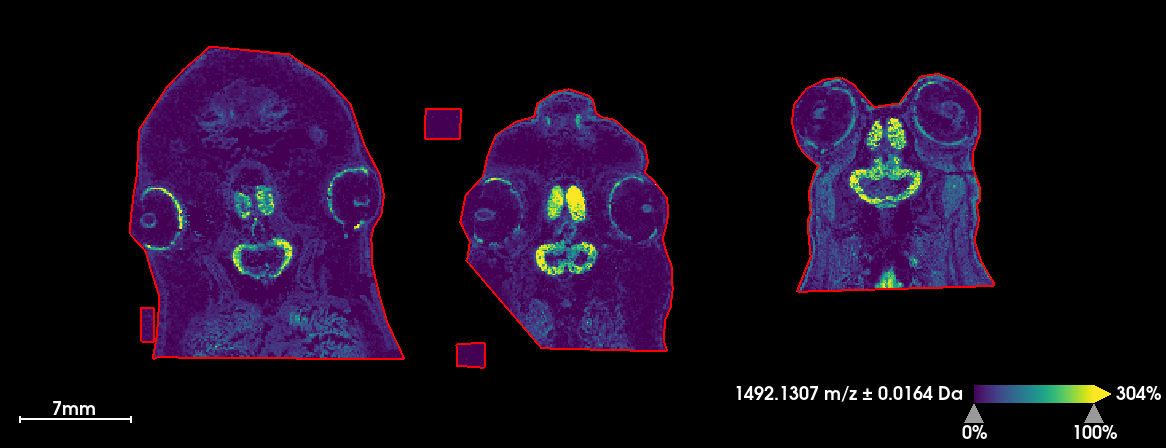

Amphibians are exceptional alternative models because the action of thyroid hormones on the re-organization of a tadpole brain during metamorphosis has direct parallels to the developing human brain during the last trimester and the first weeks of life where a surge of thyroid hormones is essential for proper development. Using mass spectrometry imaging we initially developed a methodology to examine a whole developmental series of tadpoles throughout metamorphosis to establish a critical developmental baseline and produce a brain developmental atlas applicable to other vertebrate species as well.

Mass spectrometry imaging MSI combines microscopic imaging with mass spectrometry to interrogate surfaces and in that way unites mass spectrometry and histology. This opportunity to gain spatial and chemical information has allowed us to make a developmental atlas of vertebrate brain development

Additionally, applying mass spectrometry imaging of the tadpole sensory system including brain, olfactory system and eyes after exposure to the legacy contaminant PFOS allowed an unprecedented scientific discovery as we found this contaminant to localize to a specific neuroendocrine gland and to the olfactory epithelium.

MSI of tadpole brains